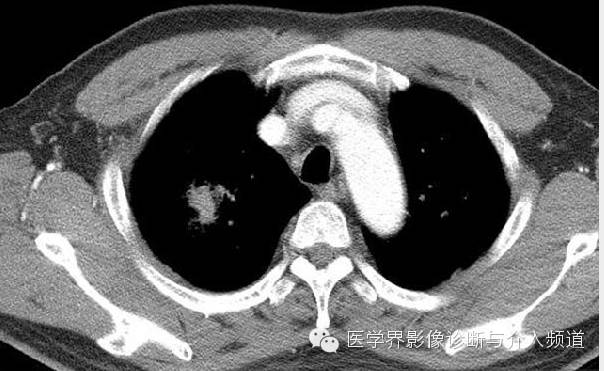

CT显示右肺上叶实性团块病灶内不规则空洞形成,周围可见GGO,右侧胸腔少量积液。患者外周血嗜酸性粒细胞增多和Pw抗体阳性。治疗后X线平片显示右上肺结节影缩小。治疗前X线片显示病灶位于右肺上野,右侧肋膈角变钝。此外,X线平片示主支气管节段性偏心性狭窄,这是由于胸内甲状腺肿外在压迫所造成。